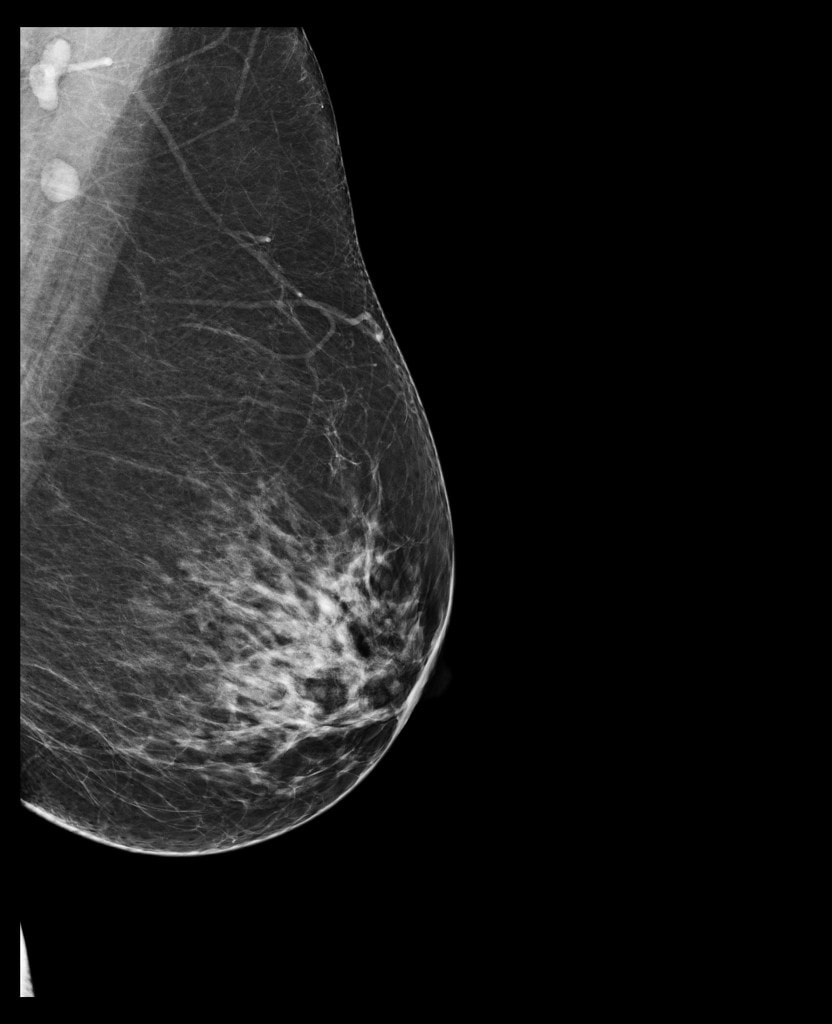

– Tessék derékig levetkőzni. Lépjen közelebb. Hajoljon kicsit le. Ne dugja a képbe a karját. Az állát fordítsa el. Most eressze le a vállát. A testével forduljon a fal felé. Dőljön előre kicsit. Fogja meg a másik kezével a rudat. Ne mozogjon. Nem jó, homályos lett, még egyszer. Ja, ezt itt el lehet forgatni. Ez egy új gép, most tanuljuk mi is. Most a másikat. Azt hittem, ez majd jobban megy. Ne rogyassza be a térdét. Húzza ki magát. Most dőljön a gép felé, és forduljon, ahogy az előbb, csak fordítva. És kicsit hajlítsa be a térdét. Öltözzön fel és üljön le kint.

– Vetkőzzön le a függöny mögött derékig. Mindent hagyjon ott. Adok lábzacskót. Adja ide a régi felvételeit. Nézzük. Ez a bal, ez a jobb. Feküdjön le. Nem, fordítva. Ez mikori? Mondtam, hogy feküdjön le. A régi CD-jét nem tudjuk beolvasni, új a gép. Ma dolgozunk vele először. Aha, ide vetíti a balt, ide a jobbat. Nem, először a bal két felvételét, aztán a jobbét együtt, összerakja. Feküdjön már le, mit nézeget. Látod, ez a kettő jön fel először. Na nézzük. Feküdjön hanyatt. Forduljon felém. Úgy, nagyon jó. Készen vagyunk. Ezt kiveszem maga alól, ezzel megtörölközhet.

kép | healthimaging.com